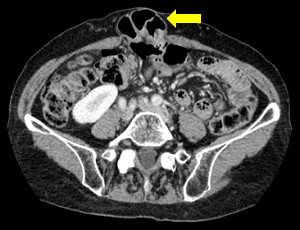

�@�l�a�i�������j�w���j�A

�{���Ȃ炨���̒��ɂ���͂��̕����⒰�̈ꕔ���A�l�a���i�l�a�Ƃ͉��������瑫�̕t���������̂��Ɓj�̕��ǂ̎ア�����畠���̈ꕔ���X�i�ӂ���j�ƂȂ��ēˏo���A�畆�̉��ɏo�Ă���a�C�ł��B��ʓI�ɂ͒E���i�������傤�j�ƌĂ�܂��B ���c�����獂��҂܂ŕ��L���N���肤��a�C�ł��B���c���̏ꍇ�͐�V�I�ȗv�����قƂ�ǂł����A���l�̏ꍇ�͉^���s�����܂ߐg�̂̑g�D���キ�Ȃ邱�Ƃ��v���ł��B ����40�Έȏ�̒����N�j���ɑ����݂��܂��B |

��ڃw���j�A�́A�l�a�w���j�A�����������ɋ߂��Ƃ��낪�c�i�ӂ��j��ރw���j�A�ł��B

�����Ƃ��ẮA�l�a�w���j�A�Ɠ����悤�ɁA����Ȃǂɂ��ؓ���ؖ����キ�Ȃ邱�Ƃ�A�d�����������ȂǕ�����������₷����Ԃ��������Ƃ��ɋN����₷���ƌ����Ă��܂��B

��ڃw���j�A�͒��N�ȍ~�̏����ɑ����݂��܂��B���ɁA�o�Y�𑽂��o���������i��j���^�̏����ɑ����ƌ����Ă��܂��B���̗��R�Ƃ��ẮA�����͒j���ɔ�ׁA��ڗցi�����������j�ƌĂ��l�a�Ցсi�����j�̉��̌��Ԃ��L�����ƁA�o�Y�ɂ���ڗ֎��͂̋ؓ���ؖ����キ�Ȃ邱�ƂŁA���Ȃǂ������̒�����o�Ă��₷���Ȃ邱�ƂȂǂ���<�����܂��B